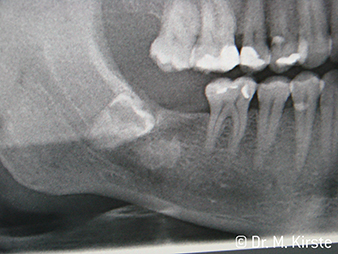

Raggi X W&H

Figura 6:

Esempio di paziente: il dente malposizionato 48 ...

Esempio di paziente W&H

Figura 7:

... viene estratto con facilità grazie al nuovo contrangolo.